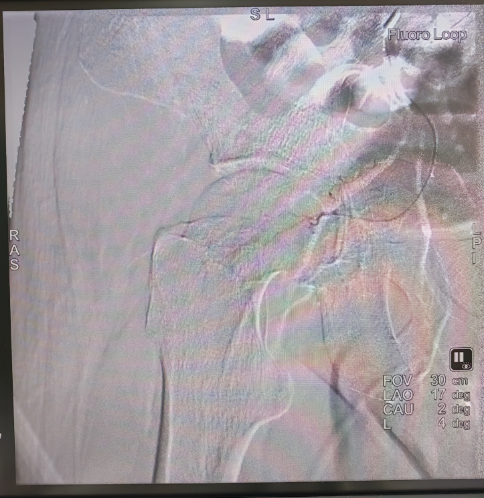

手术在高精度数字减影血管造影机(DSA)的实时引导下,采用局部浸润麻醉,通过穿刺患者大腿根部的股动脉,置入5F血管鞘,将一根5F的造影导管先后插入髂内动脉、髂外动脉内进行血管造影,辨识股骨头的供血动脉,随后将2.7F的微导管分别超选择性的插入到患侧的股骨头供血动脉,并经微导管逐一向病变区域的供血动脉注入溶栓、解痉、扩血管和改善股骨头微循环的药物。手术历经2小时顺利完成,整个手术过程患者处于清醒状态,随时与手术医师交流治疗体验。